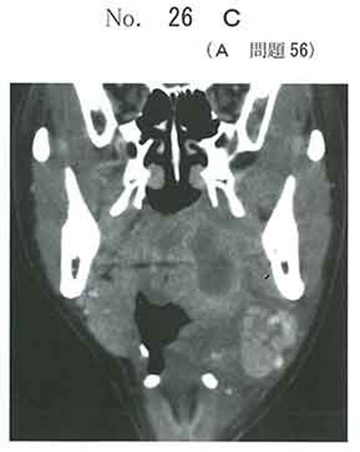

診断) 咽後膿瘍

根拠) 画像所見+炎症所見(SIRS+ 呼吸数は不明)

急性喉頭蓋炎のように,今後気道閉塞が進行するような病態ではなく,

呼吸困難の症状も無いので気管挿管は不要と考えます.